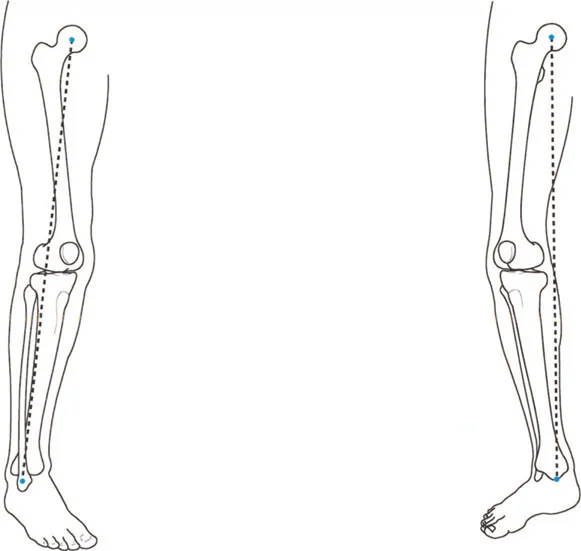

3. تحميل المفصل غير الطبيعي ومتجه رد فعل الأرض (GRV)

متجه رد فعل الأرض (Ground Reaction Vector - GRV) هو القوة المحصلة التي تؤثر بها الأرض على القدم عند نقل وزن الجسم أثناء الوقوف. يتم تحديدها بواسطة قانون نيوتن الثالث. في طرف سفلي متوافق تمامًا، يمر متجه رد فعل الأرض مباشرة عبر مركز مفاصل الورك والركبة والكاحل في كل من المستويين الأمامي والسهمي. وهذا يضمن توزيعًا متساويًا وفسيولوجيًا لقوى الضغط عبر الغضروف المفصلي.

تزيح تشوهات العظام متجه رد فعل الأرض بعيدًا عن مركز المفصل، مما يخلق عزم دوران مرضيًا.

أمراض المستوى الأمامي (التقوس/الفحج - Varus/Valgus):

إذا كان المريض يعاني من تشوه تقوس (Varus) في عظم الساق أو الفخذ، فإن متجه رد فعل الأرض يتحرك نحو الداخل (إنسيًا). كلما مر متجه رد فعل الأرض أكثر إنسيًا بالنسبة لمركز الركبة، زاد عزم دوران التقريب. وهذا يزيد بشكل كبير من قوى الضغط على الجزء الإنسي من سطح عظم الساق القريب (medial tibial plateau).

بينما يحمل الوقوف على ساق واحدة طبيعيًا الجزء الإنسي بحوالي 75%، فإن تشوه التقوس الشديد (الذي يسبب انحرافًا كبيرًا في المحور الميكانيكي، أو MAD) يمكن أن ينقل 100% من الحمل إلى الجزء الإنسي. على مدى فترات طويلة، يؤدي هذا التحميل الميكانيكي الموضعي المفرط إلى تدهور سريع وتدريجي للغضروف المفصلي، وتصلب تحت الغضروف، وتكون نتوءات عظمية، وفي النهاية إلى التهاب مفصل الركبة في مراحله المتأخرة.

- ميلان الحوض (Pelvic Obliquity): غالبًا ما يكون تعويضًا عن اختلاف في طول الساق (LLD). يقوم المريض بخفض الحوض في الجانب الأقصر.